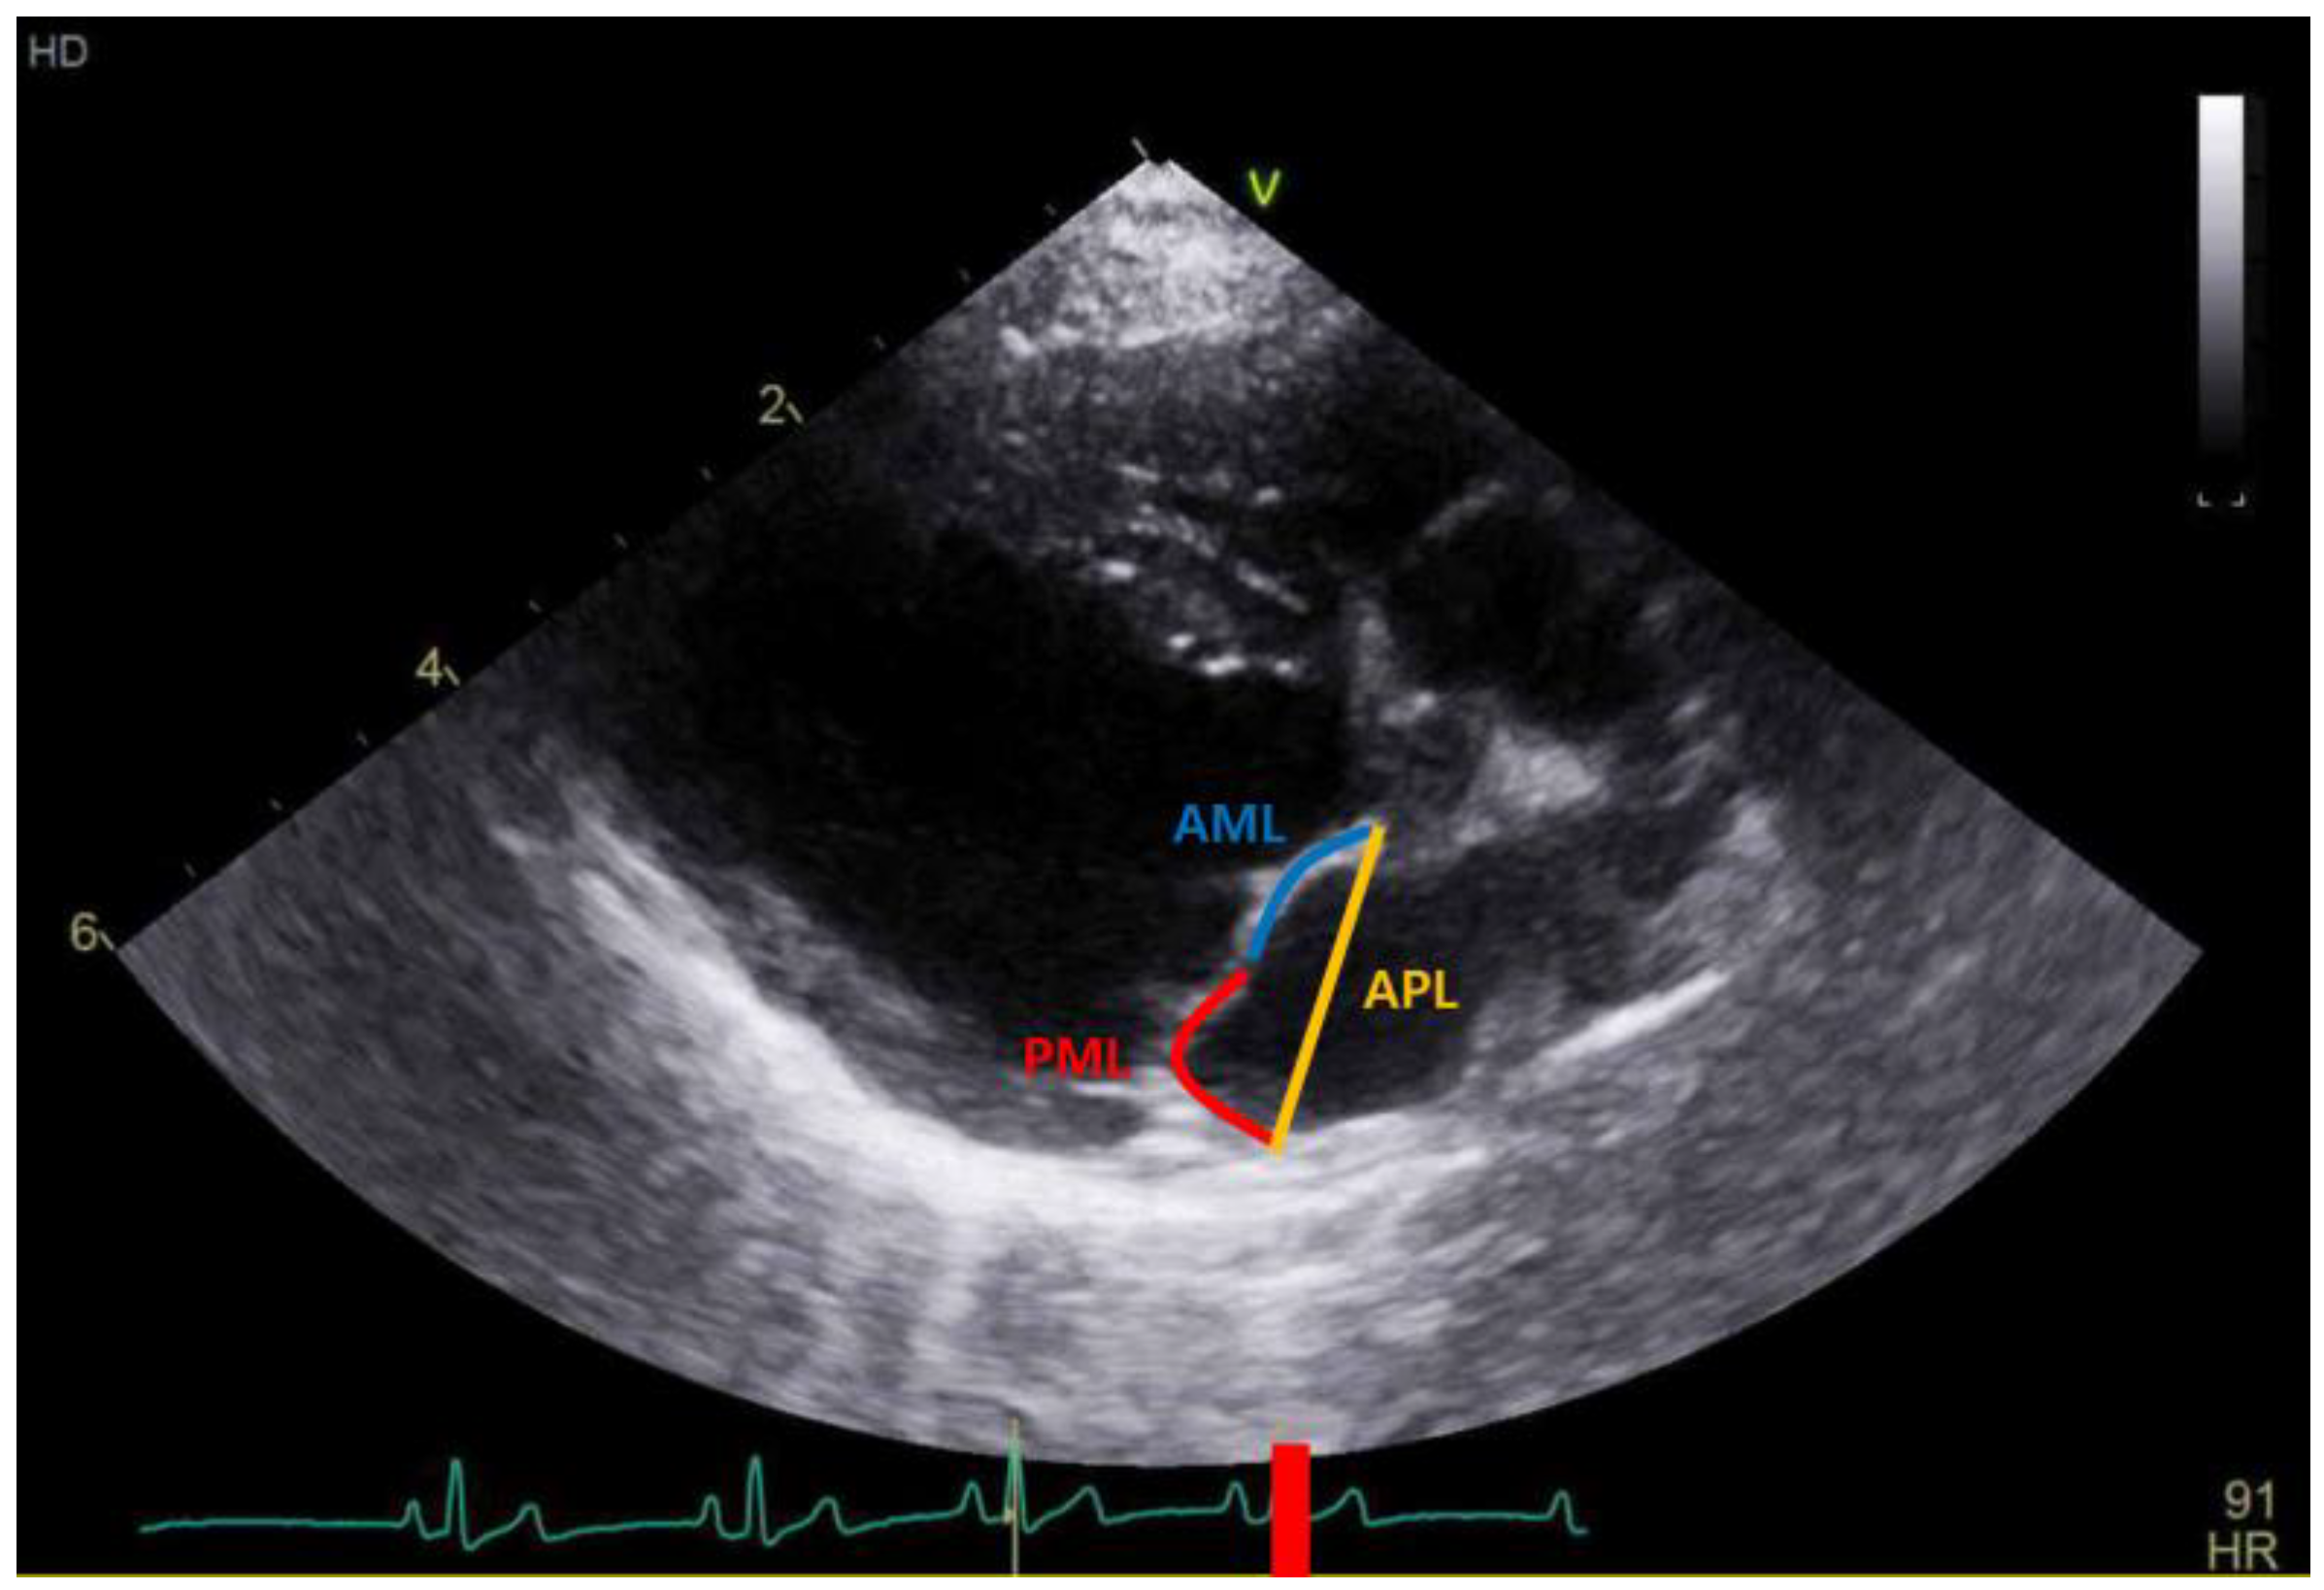

2.3. Echocardiography

| APL (mm) | 15.15 (13.09–17.55) | 16.74 (15.08–18.23) | 19.89 (17.45–22.54) | <0.001 | a,b < c α,δ,ε |

| LAI | 1.27 (1.21–1.37) | 1.14 (1.10–1.20) | 1.07 (1.05–1.14) | <0.001 | c < b < a β,γ,ε |

| LAI | −0.367 ** | −0.356 ** | −0.432 ** | −0.334 ** | −0.392 ** |